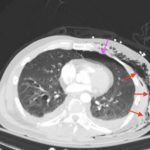

Plain film anteroposterior (AP) radiography of the chest shows left-sided subcutaneous emphysema (red arrow) with overlapping muscle striations of the pectoralis major (green arrow). After chest tube placement (blue arrow), AP chest radiography shows persistent left-sided subcutaneous emphysema (red arrow). CT of the chest shows pneumomediastinum (blue arrow), left apical pneumothorax (pink arrow), and subcutaneous emphysema (red arrow) at the level of T2. At the level of T6, rib fractures can be visualized on the CT (yellow arrow). At the level of T8, left sided pneumothorax is also seen (pink arrow) as the absence of lung tissue on CT.

In this patient, given the findings of multiple bilateral rib fractures, bilateral hemothorax/pneumothorax and multiple spine fractures, bilateral chest tubes were placed which had immediate output. The patient was admitted to surgical intensive care unit for chest tube management, pulmonary hygiene and further management of his other injuries.